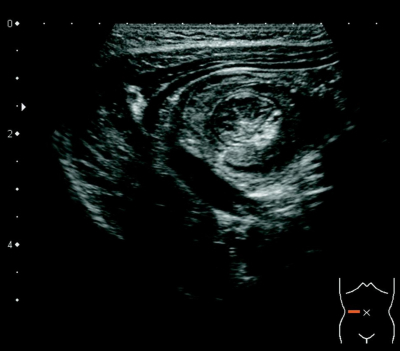

身長 86 cm、体重 11.5 kg。意識は清明。体温 36.8 ℃。脈拍 100/分、整。血圧 96/60 mmHg。呼吸数 24/分。心音と呼吸音とに異常を認めない。腹部はやや膨満しているが軟らかい。臍上部の圧痛を認める。腸雑音はやや亢進している。腹部超音波像を別に示す。

考えられる疾患はどれか。

b. 腸重積症